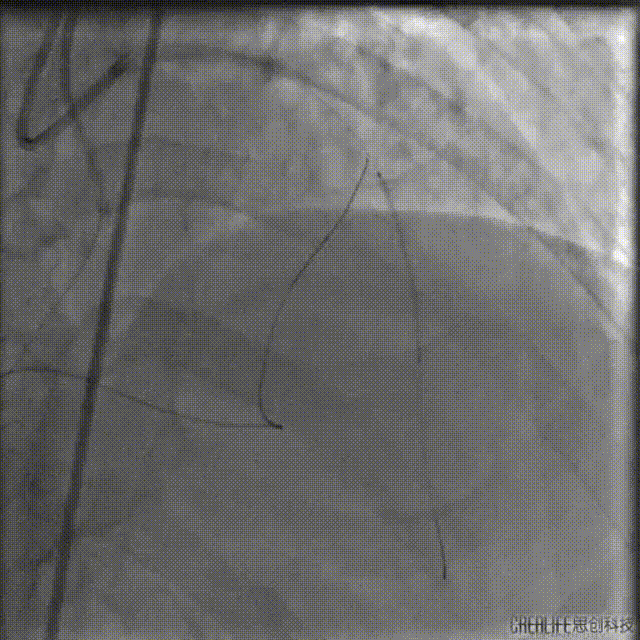

2.5*15mm球囊后扩时球囊发生断裂,导丝旋转缠绕后撤出左侧指引导管。

球囊杆断裂的处理方法:

断端在GC内:球囊断开的软段还在GC内,选择再送入导丝和球囊锚定后撤出。

断端在升主动脉:使用抓捕器,尤其断裂段在升主动脉,球囊断端以远没有坚硬的部位,紧紧抓住后收到GC内也是很好的方法,注意精细操作抓捕。

断端在冠脉内:选择抓捕法或导丝缠绕法,这两种方法的困难点在于把导丝通过球囊送到远端,其中抓捕法应该比较难实现,在近段可以进行尝试,选择自制抓捕器,同时使用延长导管辅助抓捕。对于缠绕法,需考虑导丝从支架中心腔通过的问题,还包括导丝能否顺利缠绕,能否顺利回拉,延长导管能否成功跨过血管近段病变跟入等等困难。

IVUS查看见支架远端局部血肿,遂远段植入2.25*29mm支架,并送入2.5*15mm球囊后扩,并用4.0*12mm球囊后扩近段支架。

最终造影结果

复查造影未见明显狭窄,TIMI血流3级。